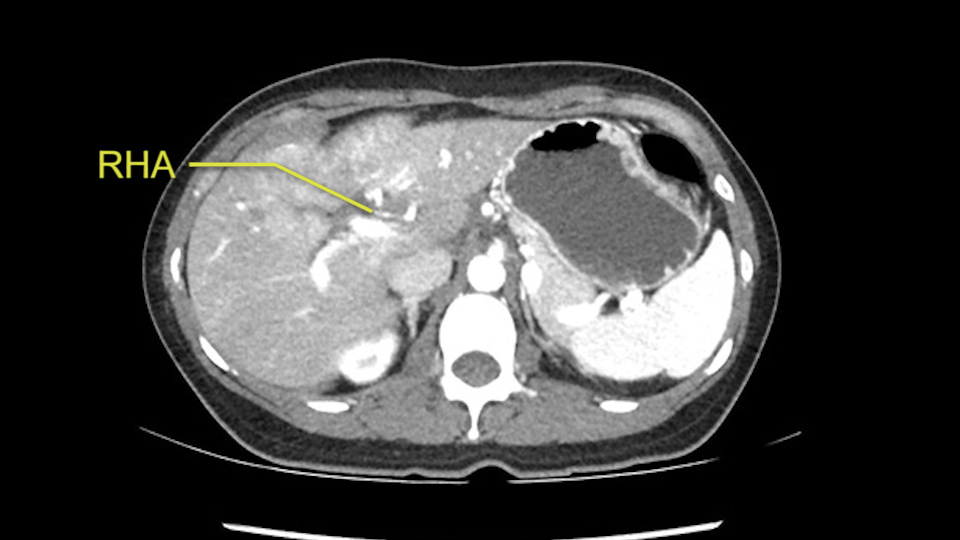

The second is the left hepatic artery. The tumor is displacing the arterial system. So one of the important points which we need to see intraoperatively is to identify and preserve the right artery very carefully and identify the left hepatic artery for ligation.

RHA, Sg4 artery not involved in tumor

So in planning for this operation, as I look at the scans, I first visualize the arterial phase and I can see that there’s are a lot of big feeding arteries to this large tumor. Likely all the right side vessels feeding the right side of the liver: right hepatic artery and likely the Segment 4 artery are spared from the tumor. It’s likely the left hepatic artery is ramificating and giving feeding arteries to this tumor. It certainly looks like a large mass that its compressing other structures like the cava, the pancreas, the stomach; but I think there’s a plane and we can see that better in the venous phase. There’s a plane of separation between the gallbladder, the pancreas, the cava, that this tumor is abrupting but likely not invading. Usually, these masses actually don’t invade at that level and basically are pushing the tissues and once you open, you’re able to separate the tumor. Sometimes there’s some adhesions but you can actually separate and there’s usually no invasion.